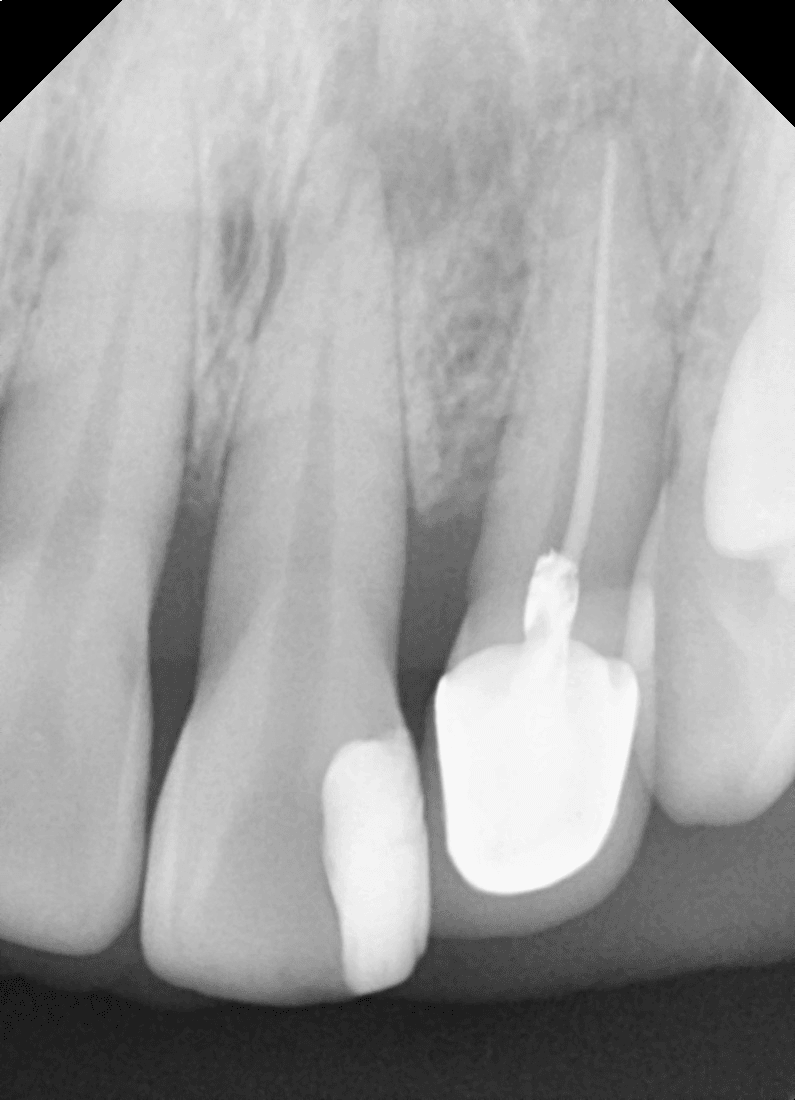

잇몸 속에 묻혀 있던 임플란트를 노출시키고

보철물을 연결하기 위한 과정입니다.

1차 수술 후에는 임플란트가 잇몸뼈와 단단히 결합되는 시간을 갖게 되며,

이 과정이 끝난 후 2차 수술을 통해 기둥(어버트먼트)을 연결하게 됩니다.

절개 범위가 크지 않아 통증이나 회복 부담은 비교적 적은 편입니다.